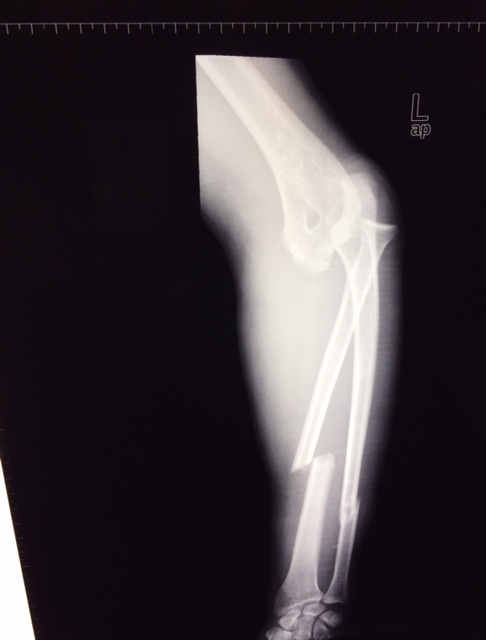

Парень, 24г., Авария, ЧМТ, перелом обеих костей предплечья, вывих локтевого сустава и перелом короноида (?).Рана 1 см, ушита при поступлении. Без осложнений, кисть - норм. функция.

КТ не делали.

Полностью стабилен, неделя после травмы.